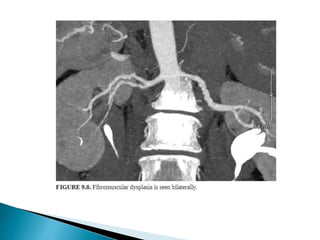

1. Atherosclerosis.

2. FMD

3. Accessory renal artery.

4. Duplicated renal artery.

5. Triplicated renal artery.

6. Occluded small lower polar arteries.

7. Short distance between the origin and first

bifurcation of all major renal arteries.